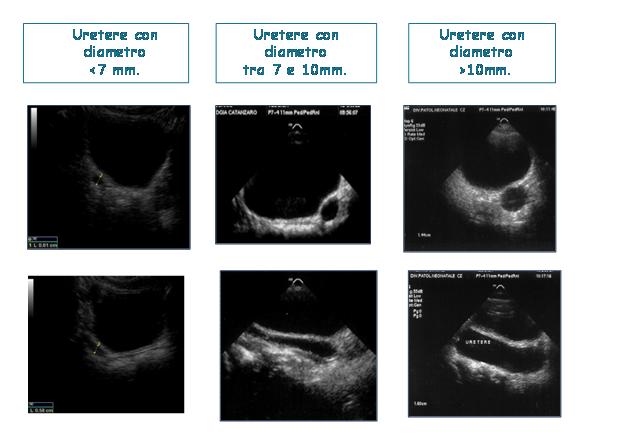

Una Classificazione puramente morfologica, basata sulla valutazione ecografica del calibro dell�uretere ectasico � quella proposta dalla Society for Fetal Urology6 che distingue i megaureteri in tre gradi (Figura 1):

grado 1: diametro ureterale inferiore a 7 mm;

grado 2: diametro ureterale tra 7 e 10 mm;

grado 3: diametro ureterale superiore a 10 mm.

Figura 1. Classificazione ecografica del megauretere secondo la S.F.U